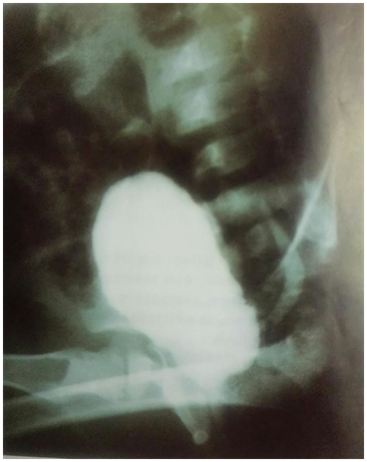

The patient micturating cystourethrogram (MCUG) showed large filling defect arising from the posterior wall of the urinary bladder with secondary left VUR.

After one year of follow-ups, the opened cystostomy and marsupialization of the ureterocele, MCUG was performed and showed irregular wall of the urinary bladder, right sided (VUR), with severe tortuosity dilatation of the ureter and severe hydronephrotic changes in the collecting system of right kidney, with Lt secondary VUR (Figure 3).

Figure 3 MCUG after marsupialization of the obstructed ureterocoele: showed severe right VUR 5 degree and secondary left VUR.